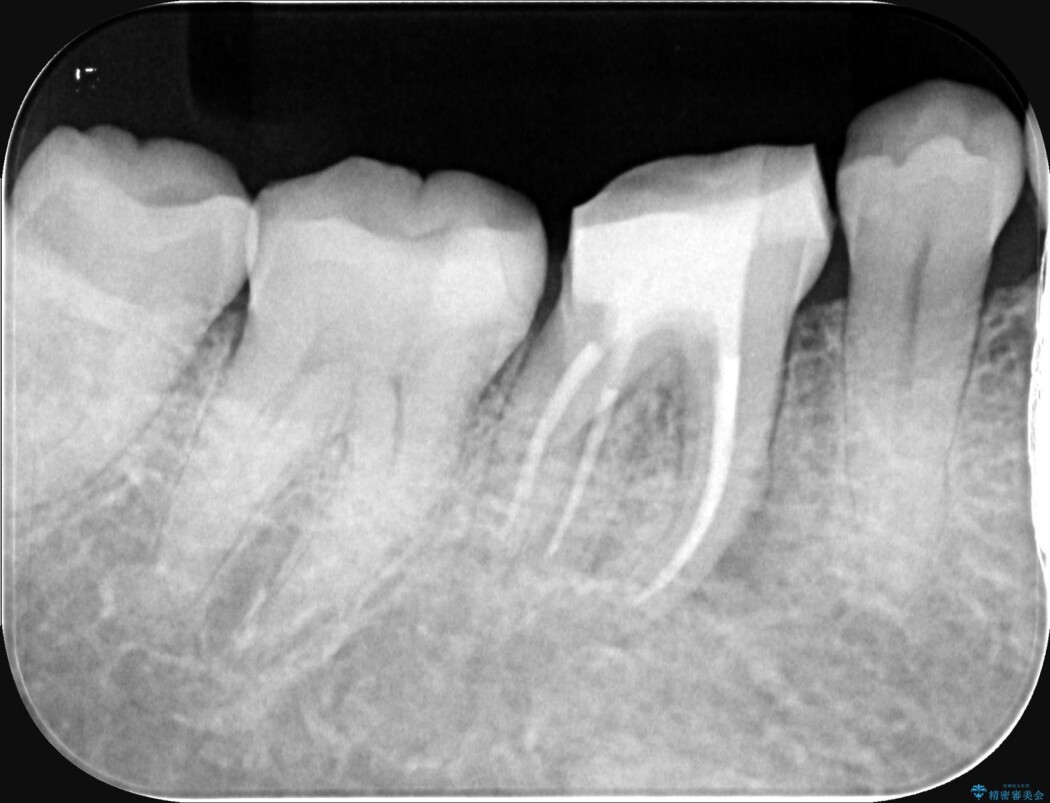

治療では、マイクロスコープで根の中を大きく拡大し、非常に細くなっていた神経の通り道を慎重に見つけ出しました。

次に、根のカーブに沿ってしなやかに曲がるニッケルチタンファイルを使い、根の先まで徹底的に洗浄・殺菌を行いました。汚れを完全に取り除いた後、隙間なくお薬を詰めて密閉しています。

術後の経過は非常に良く、あんなに大きかった膿の袋は消え、健康な骨が再生しているのが確認できました。痛みや腫れも消えて抜歯を免れ、現在は被せ物を入れてしっかりお食事を楽しんでいただけるようになっています。